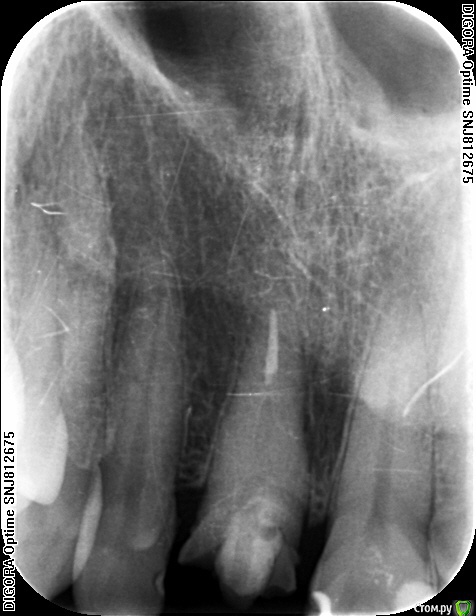

Популярный пост an_ver Опубликовано 15 января, 2016 Популярный пост Поделиться Опубликовано 15 января, 2016 11,жил долго и счастливо..но тут Новый год(((, скол ниже уровня ЦЭС на 3 мм...от экструзии отказалась.Из своего зуба сколхозил шаблон,чтоб наверняка. Удалил,кюретаж,вестибулярка целая, SPI 4.2*13 мм,с бугра ССТ,на всякий)),в щели Апатос,врем.абатмент,врем.коронка из своего зуба. 1ч.20мин.)) 27 Ссылка на комментарий